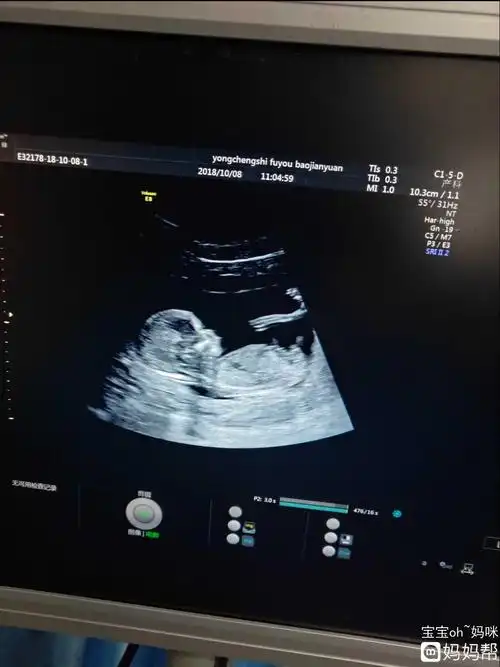

研究nub理论,nt图发来帮看男女,必回

nt怎么看男宝还是女宝 已生宝妈告诉你答案

nt看男女,准确吗?

nt通过啦!有伙伴会看男女嘛